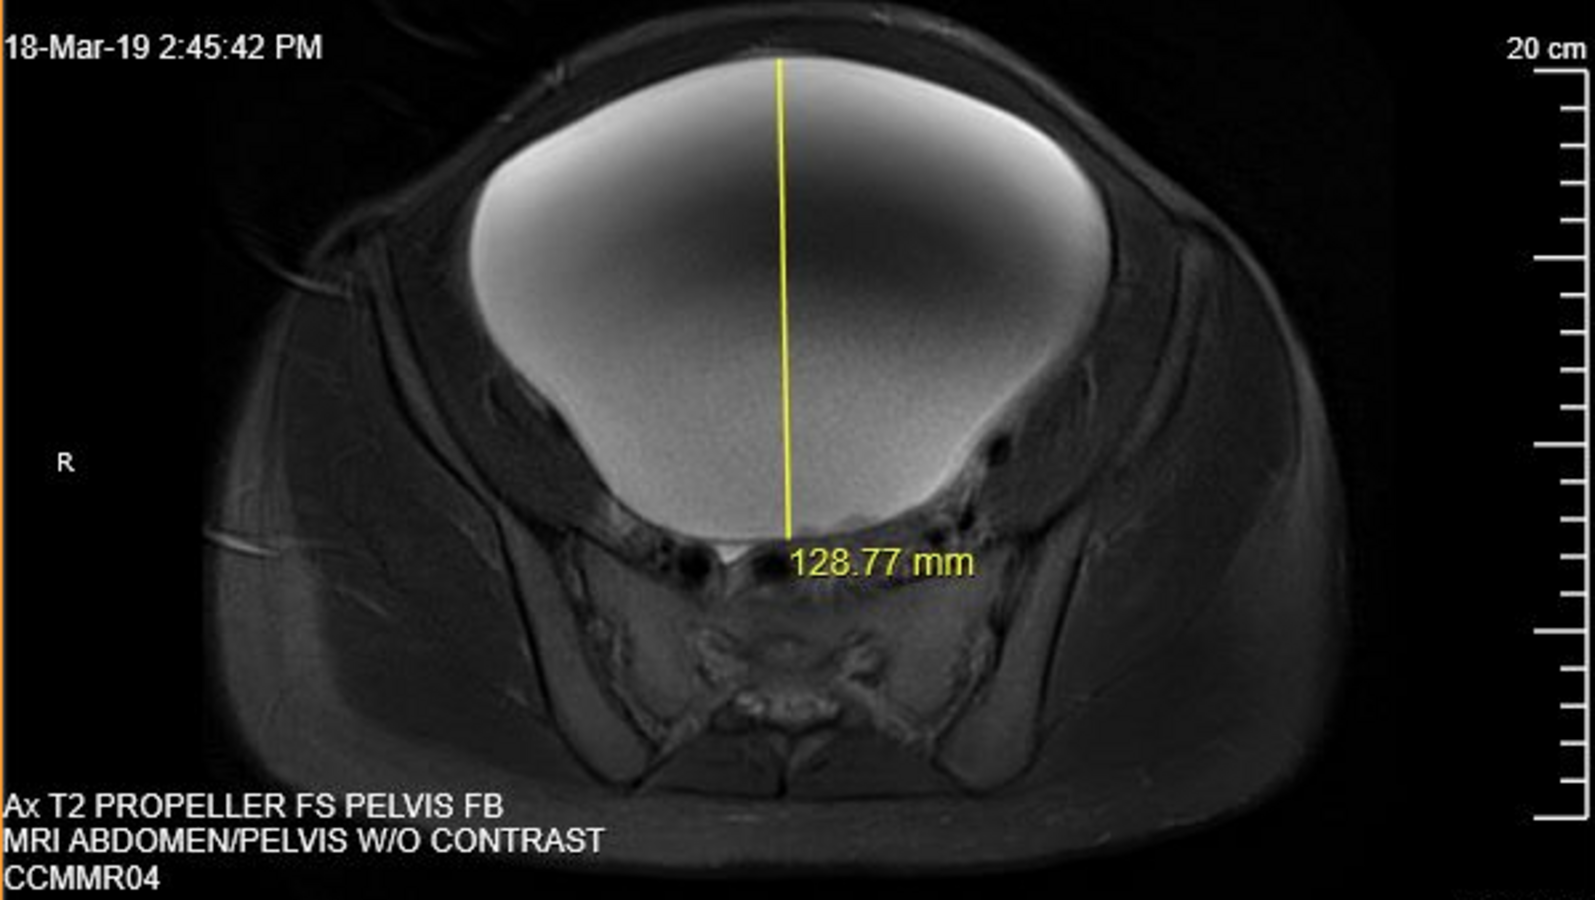

The mass appeared as a unilocular cyst with smooth contours, suggesting a benign etiology (Figures 3 and 4). No evidence of acute urinary or bowel obstruction was noted. A chest radiography scan was also conducted, results of which did not show evidence of metastatic disease. Ovary-sparing surgical excision of the cyst was conducted. The patient’s post-operative course was uneventful, and she was discharged home on post-operative day 2.